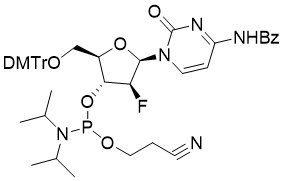

馬鞍山致研生物醫(yī)藥科技有限公司成立于馬鞍山市鄭浦港新區(qū)現(xiàn)代產(chǎn)業(yè)園。公司專(zhuān)注于生物小分子、醫(yī)藥中間體相關(guān)產(chǎn)品的研發(fā)和生產(chǎn),產(chǎn)品主要包括DNA亞磷酰胺單體、RNA亞磷酰胺單體、特殊單體以及按照客戶(hù)要求定制的RNA和DNA,并且公司提供定制合成等方面的研究服...

馬鞍山致研生物醫(yī)藥科技有限公司成立于馬鞍山市鄭浦港新區(qū)現(xiàn)代產(chǎn)業(yè)園。公司專(zhuān)注于生物小分子、醫(yī)藥中間體相關(guān)產(chǎn)品的研發(fā)和生產(chǎn),產(chǎn)品主要包括DNA亞磷酰胺單體、RNA亞磷酰胺單體、特殊單體以及按照客戶(hù)要求定制的RNA和DNA,并且公司提供定制合成等方面的研究服...